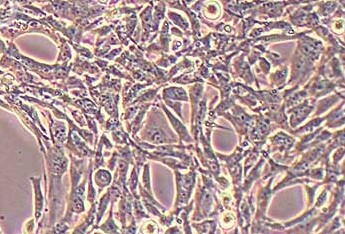

简介 小鼠耳蜗毛细胞系House Ear Institute-Organ of Corti 1(HEI-OC1)来源于小鼠耳蜗。该细胞用于研究小鼠听觉研究,被认为是一种用于筛选耳毒性药物的体外系统,已被用于研究药物激活的凋亡途径、自噬、衰老、炎症反应、细胞分化、药 物的遗传和表观遗传的作用,还有耳蜗中分子通道和受体的表达。

形态 上皮